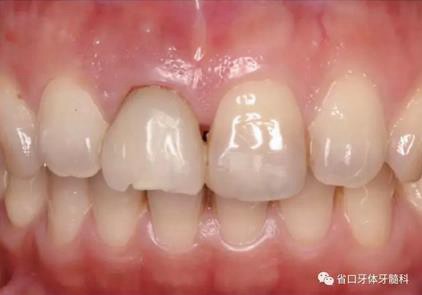

圖1 術(shù)前口內(nèi)照

圖2 術(shù)前口內(nèi)照

圖3 術(shù)前口內(nèi)照

1.?病例簡介 43歲女性患者,主拆:右上前牙松動(dòng)不適數(shù)日要求修復(fù)?,F(xiàn)病史:患者數(shù)年前右上前牙因“齲壞”于外院行根管治療(具體不詳),數(shù)日前牙冠松動(dòng)不適,現(xiàn)覺影響咀嚼及美觀,遂來我院要求進(jìn)一步診治。否認(rèn)高血壓、心臟病等重大疾病,否認(rèn)結(jié)核、肝炎等傳染病史,否認(rèn)手 術(shù)、輸血史等,未發(fā)現(xiàn)藥物過敏。無吸煙習(xí)慣。臨床檢查:口外觀顏面基 本對稱,皮膚無紅腫破潰,顳下頜關(guān)節(jié)區(qū)無彈響、雜音、壓痛,開口度約 37mm,開口型“↓”,頜下、刻下和頸部未及腫大淋巴結(jié)。中位笑線??趦?nèi)檢查,口腔衛(wèi)生可,色素(+),BOP(-),PD=2mm,上頜右側(cè)中切 牙冠部變色,冠根折斷至齦下3mm,叩不適,松動(dòng)Ⅱ°~Ⅲ°。牙齦稍紅, 齦緣水平及齦乳頭高度可,屬于中厚齦生物型,附著齦寬度約5mm,唇系帶附著可。上頜右側(cè)中切牙缺牙間隙與對側(cè)同名牙一致,約>7mm,修復(fù)空 間良好。與對頜牙覆合覆蓋正常。MCT檢查示上頜右側(cè)中切牙冠根折斷至骨 下,根管內(nèi)見充填物,根充不全,根尖見陰影,大小約3mm×3mm。牙槽窩根方可用骨量可,唇側(cè)骨壁完整,冠方骨壁厚度約1mm。